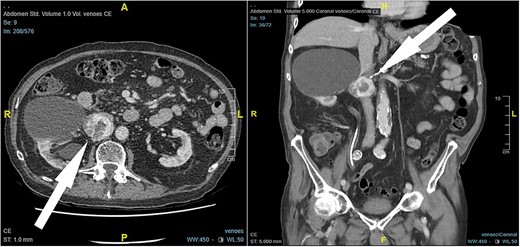

An 87-year-old male Caucasian patient with a history of cardiac co-morbidities, diabetes mellitus type 2, and chronic kidney disease stage 4 was referred to our hospital for clinical evaluation and a non-contrast abdominal–pelvic CT scan because of right side pain with a history of kidney stone disease, with recurrent ureteral stones. The CT scan showed a small distal ureteral stone on the right side without the need for surgical intervention. Incidentally, he had a retroperitoneal mass (4.4 × 4 × 4 cm) posterior to the inferior vena cava, with compression on the inferior vena cava and the right renal artery (Fig. 1). Our radiologist classified this unexpected incidental finding as a possible neuroendocrine tumor, with the recommendation to perform a DOTATE-PET/CT scan. The DOTATE-PET/CT showed a sizeable retrocaval mass with edge-accentuated radionuclide storage, compatible with a paraganglioma or a lymph node metastasis of a neuroendocrine tumor (Fig. 2). The ultimate etiology remained unclear, despite the radiological scans. Our blood tests showed a normal level of hormones in the blood and urine, excluding hormonally active tumors. The only noticeable value in the blood was the elevated creatinine as a part of the chronic kidney disease. One of our assumptions was that the tumor compression on the renal artery impacts the patient’s kidney function. The patient reported no remarkable symptoms.

DOTATE-PET/CT: sizeable retrocaval mass with edge-accentuated radionuclide storage, compatible with a paraganglioma or a lymph node metastasis of a neuroendocrine tumor (arrow).